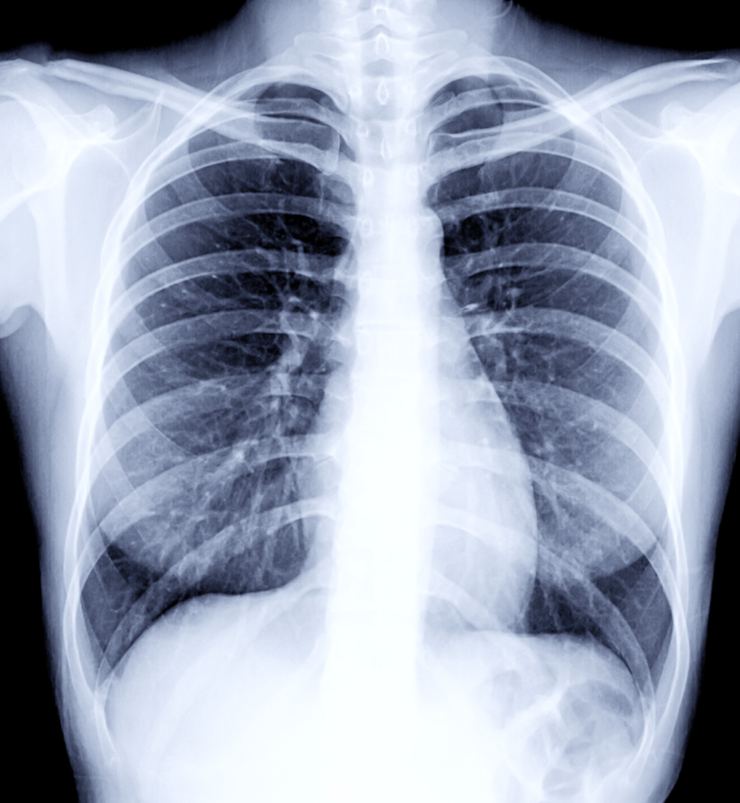

- Kovid-19 hastalığı akciğerleri hedef alan ölümcül bir hastalıktır. Bu nedenden dolayo bağışıklık sisteminin yanında akciğerleri de güçlendirmek oldukça önemlidir. Akciğerleri güçlendirmek için yapılması gerekenleri sizler için sıraladık…